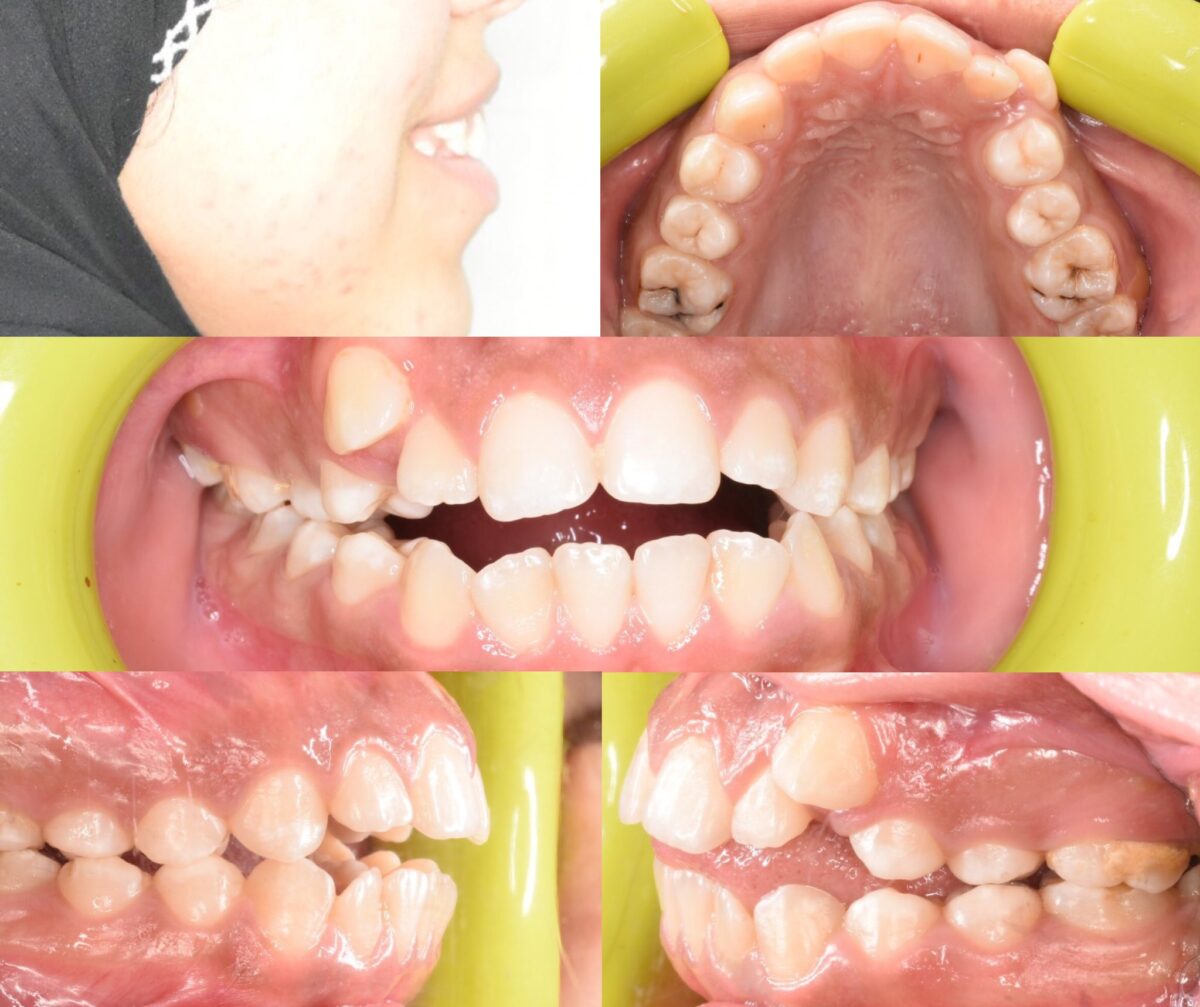

دكتور أحمد مجدي بيبدأ معاك بفحص شامل للأسنان واللثة، باستخدام أحدث الكاميرات اللي بتصور الفم من جوه وتعرض الصورة على شاشة قدامك، بحيث تشوف بنفسك المشاكل اللي محتاجة علاج. ولو الحالة تتطلب، بيعملوا أشعة بانورامية أو ثلاثية الأبعاد بتوضح أدق التفاصيل، وده بيساعد على وضع خطة علاجية دقيقة وفعالة. الأسلوب دا بيخليك شريك في قرار العلاج وفاهم كل خطوة قبل ما تبدأ.

للي محتاجين تقويم، سواء معدني أو شفاف، العيادة بتوفر أحدث حلول التقويم المناسبة لكل حالة، مع متابعة دورية لضمان تقدم العلاج بالشكل المطلوب. وكمان لو في فقدان سن، بيتم تعويضه بزرعات أسنان من التيتانيوم المعتمد دوليًا بعد فحص شامل لعظام الفك وأشعة دقيقة، لضمان أفضل ثبات ونتيجة تدوم سنين.